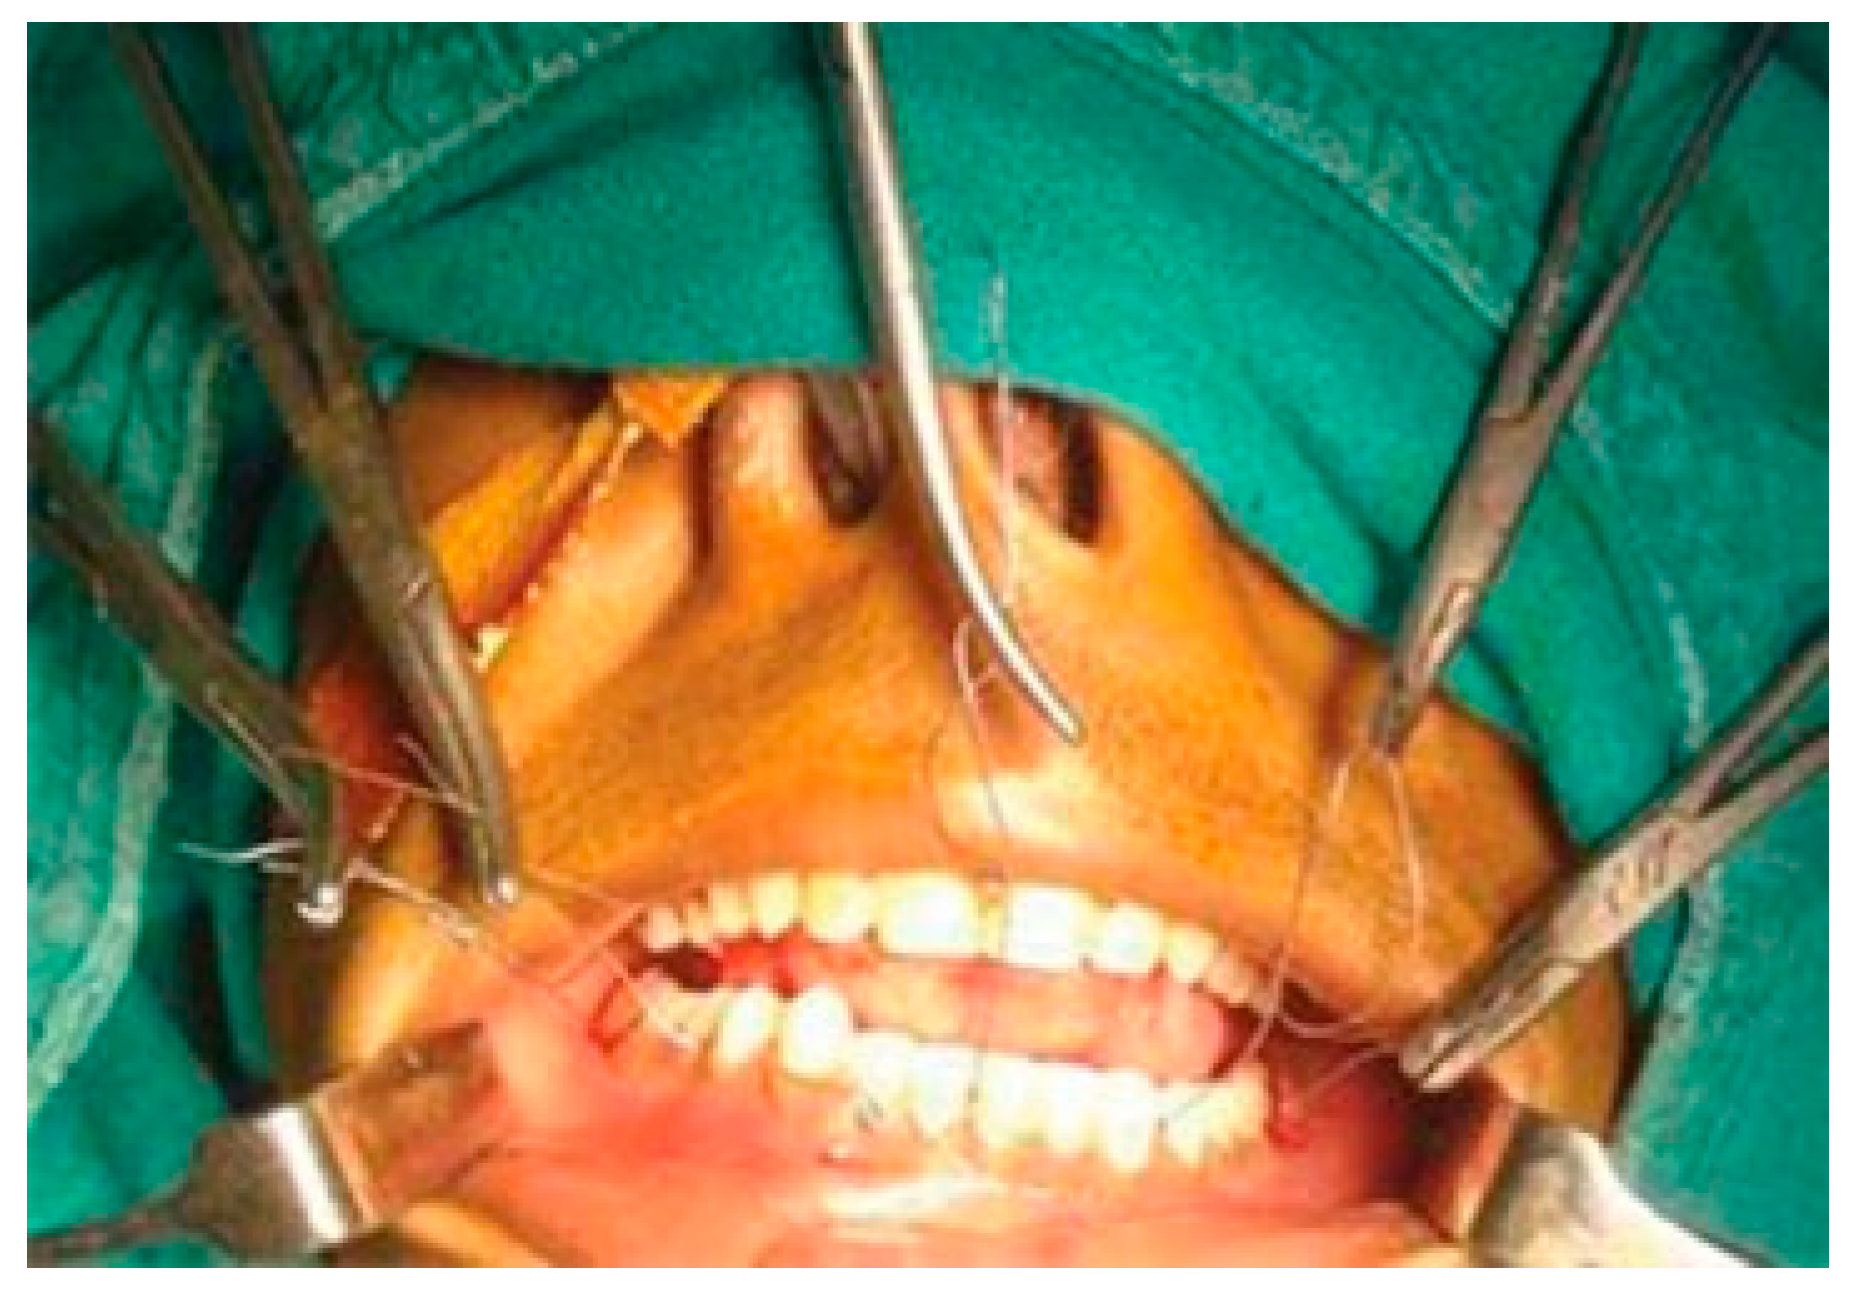

For the illustration of the technique, a case of left angle fracture with right parasymphysis fracture of the mandible has been depicted (Figure 1). With the mouth open, stainless steel wires (24 gauge) approximately 15 cm were introduced through the facial embrasure between the maxillary molars, premolars, and the maxillary central incisors. Next, the palatal end of the wire is looped and then passed through the opposing lingual embrasure in the mandible (Figure 2).

Next, the fracture sites were exposed and segments were reduced appropriately, and then all the embrasure wires were twisted together until the fixation is rigid. It is very important to reduce the fractures before twisting the wires. After achieving functional occlusion along with anatomical reduction, fractured segments are fixed with miniplates and screws (Figure 3 and Figure 4). Unlike arch bars, the embrasure wires provide superior stability, which could prevent fracture reduction once IMF has been established (Figure 5).

Figure 4. Excellent stability of anatomically reduced fractured segments after fixation.